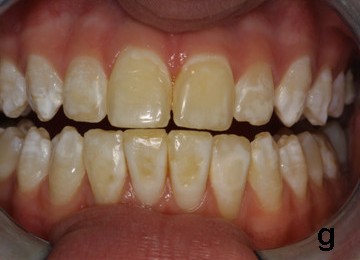

경미한 반상치의 경우, 치아 법랑질 표면은 대체로 손상되지 않고 단단하며 매끄럽지만, 경계가 불분명한 불투명한 흰색 반점이나 주름선(perikymata)을 따라 좁은 흰색 선이 나타나는 특징을 보인다.[7] 상태가 심해질수록 치아 표면 아래의 법랑질은 더욱 다공성(구멍이 많아지는 상태)이 된다. 이로 인해 법랑질은 황색이나 갈색으로 변색되거나, 충치와 유사하게 움푹 들어간 흰색-갈색 병변이 여러 개 나타날 수 있다. 이러한 외형은 흔히 "얼룩덜룩한 치아"라고 묘사된다.[8]

반상치 자체가 직접적으로 치아 변색을 일으키는 것은 아니다. 반상치의 영향을 받은 영구치가 처음 입안으로 나올 때는 아직 변색되지 않은 상태이다. 반상치는 법랑질 표면 아래에 미세한 구멍(다공성)을 만들거나 저석회화를 유발하는데, 상태가 진행되면 이러한 변화가 상아질-법랑질 경계면까지 확장된다. 이렇게 다공성이 증가한 법랑질은 외부 물질에 의한 착색에 더 취약해진다. 시간이 지나면서 음식물이나 음료 등에 포함된 외인성 이온(예: 철, 구리 이온)이 비정상적으로 다공성이 된 법랑질에 침투하여 점차 얼룩을 만들게 된다.[7]

반상치(불소증)의 적절한 진단은 시각적 임상 검사를 통해 이루어진다. 이를 위해 좋은 조명 아래에서 건조하고 깨끗한 치아 표면을 검사해야 한다.[6] 임상 증상은 개인별 불소 노출 기간, 시기, 용량에 따라 다양하게 나타난다. 경미한 경우 경계가 불분명한 흰 반점이나 선으로 나타나지만, 심해지면 법랑질이 다공성이 되어 황색/갈색 변색이나 움푹 팬 병변이 나타날 수 있다.[7][8] 이러한 외관상의 특징 때문에 다른 치아 질환과의 감별 진단이 중요하다.

반상치는 치아가 발달하는 시기에 불소를 과다 섭취하여 법랑질 형성에 이상이 생기는 질환이다.[13] 과도한 불소는 법랑질의 정상적인 광화 과정을 방해하여 표면 아래가 저석회화되고 다공성 구조를 띄게 만든다.[7] 이로 인해 치아 표면에 흰색 반점이나 줄무늬가 나타나며, 심한 경우 황갈색으로 변색되거나 표면이 패일 수 있다.[7][8] 이러한 변화는 주로 영구치에 나타나며, 시간이 지남에 따라 외부 물질에 의해 착색될 수 있다.[7]